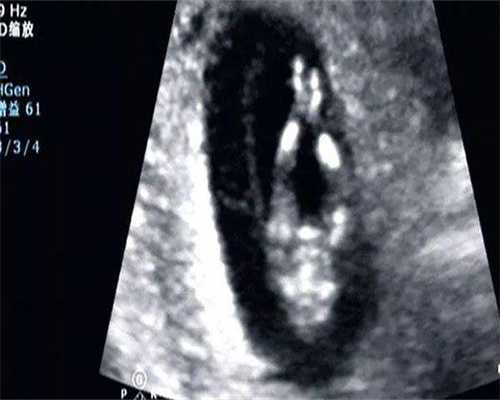

8、长沙组织供卵大约多少钱?附长沙供卵试管费用。做过许屡次精液查看,成果都不达观。可是通过长时间的药物医治,精子的状况总算有所好转,却不曾想,最大的问题是妻子的卵子。我妻子不明原因导致卵巢早衰,只做捐卵试管。湘雅能够做捐卵试管吗?

9、长沙中信湘雅排队捐卵做试管卵是免费的,由于咱们国家的捐卵来历于其他免费做了试管周期的女人。我国禁止任何方式的商业卵子捐献,只允许人道主义捐献。但一般状况下,会向捐献者付出必定的补偿费。当然,这取决于个人的志愿。假如对捐献者心存感谢,能够付出必定的补偿费,但捐献者的个人信息一般是保密的。

10、长沙捐卵试管中心,为了满意患者个性化的生殖需求,试管组织能够依据个人体检陈述在试管组织上拟定个性化计划,一起能够检测患者实时状况,及时调整计划,确保取卵质量,然后进步捐卵试管成功率。

5、长沙中信湘雅医院试管婴儿费用大约在3-10万元,首要包含前期查看费用、促排卵、取卵取精、胚胎培育、胚胎移植等手术。但捐卵试管和一般试管的差异在于,做捐卵试管的女人不必阅历促排降调理阶段,所以也能省下1-2万元左右。另一个差异在于卵子来历不同,一个来自供体,一个来自本身。